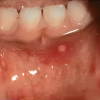

Stomatitis aphtosa

– Suu limaskestal retsidiveeruvad valulikud haavandid.

– Tavaliselt on suus 1–5 haavandit, mis on vägavalulikud.

– Haavandile ei eelne villide staadiumi nagu herpesega, teiseks erinevuseks on üldnähtude puudumine.